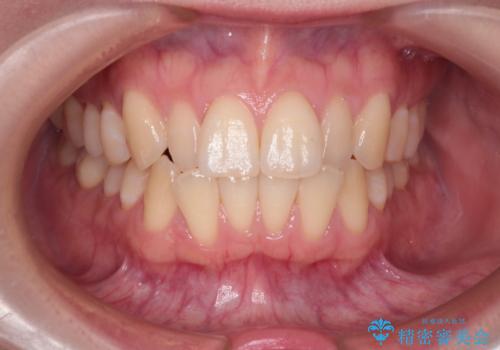

【インビザライン】反対咬合を治したい

- 前歯の反対咬合を主訴に来院されました。

インビザラインにて歯列弓の拡大により叢生の改善を行うことができ、患者様にも満足していただました。

前歯の反対咬合は歯牙への負担も大きくできるだけ早期に治療を行うことを推奨しています。